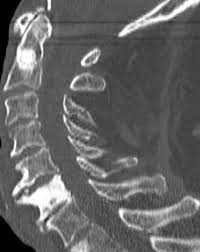

However, as with other types of cancer,. Can bone metastasis happen in the prostate cancer? Prostate cancer is one of the most common types of cancer diagnosed in men. Here are 10 more facts about prostate cancer. Find the information you need today.

The hormones that your thyroid gland produces help regulate several of your bodily functions. Prostate cancer is one of the most common types of cancer diagnosed in men. Can bone metastasis happen in the prostate cancer? The earlier the detection of prostate cancer, the better the patient's chance of survival is. Prostate cancer is a common type of cancer in men, according to the mayo clinic.